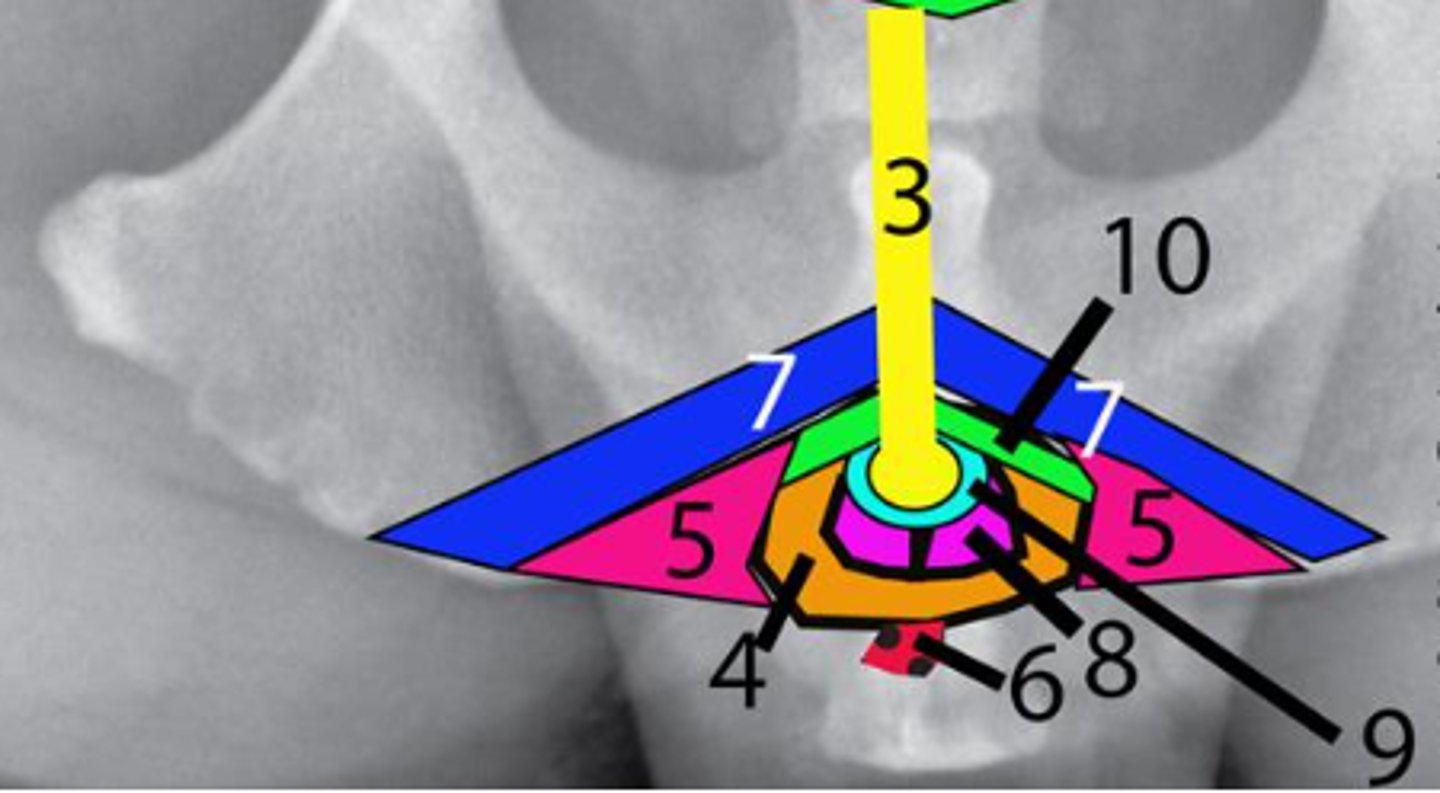

Prostate

Identify #2

Urethra

Identify #3

Bulbospongiosus muscle

Identify #4

Ischiocavernosus muscle

Identify #5

Retractor penis muscle

Identify #6

Ischiourethralis muscle

Identify #7

Bulb of the penis

Identify #8

Corpus spongiosum

Identify #9

Corpus cavernosum

Identify #10